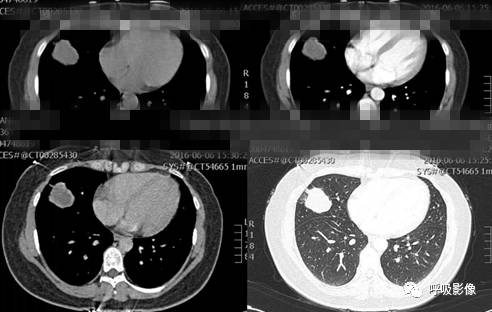

绒毛膜癌较侵袭性葡萄胎易发生转移。侵袭性葡萄胎肺部转移多以结节为主(图1),而绒毛膜癌肺部转移种类较多。

图1 女,31岁,侵袭性葡萄胎